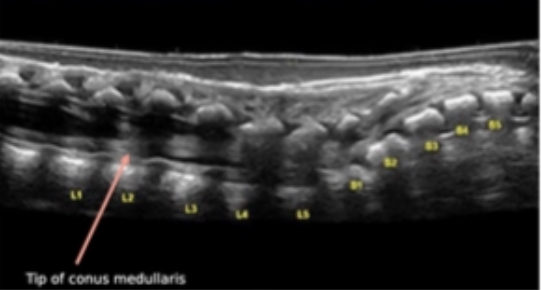

At what level does the conus end?

L2

Conus terminating at L4 with no movement is indicative of?

Tethered cord

At what level is conus abnormally low?

L3

Where does the spinal cord terminate?

conus medullaris